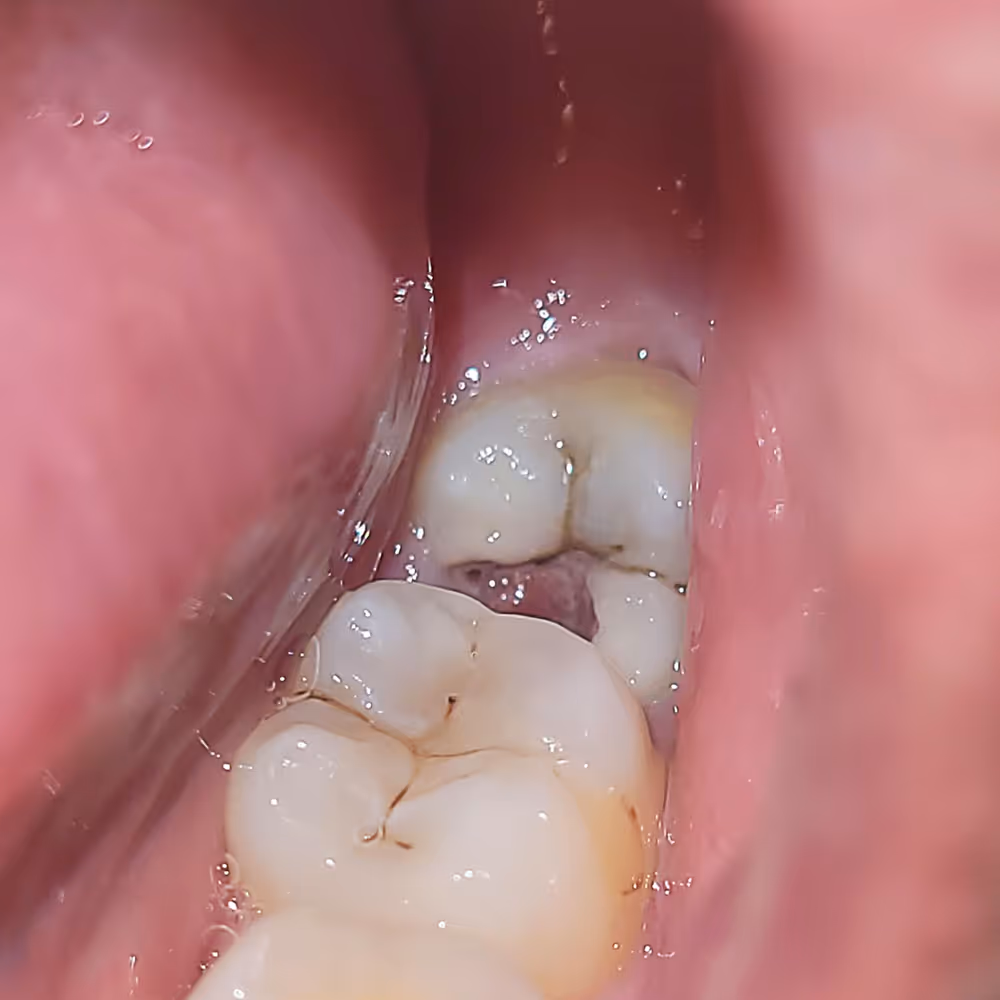

Common Problems Caused by Wisdom Teeth

At Dr. Amy’s Dental Office, we use advanced digital imaging to evaluate the position of your wisdom teeth and determine whether removal is necessary. Early evaluation helps prevent complications and supports long term oral health.